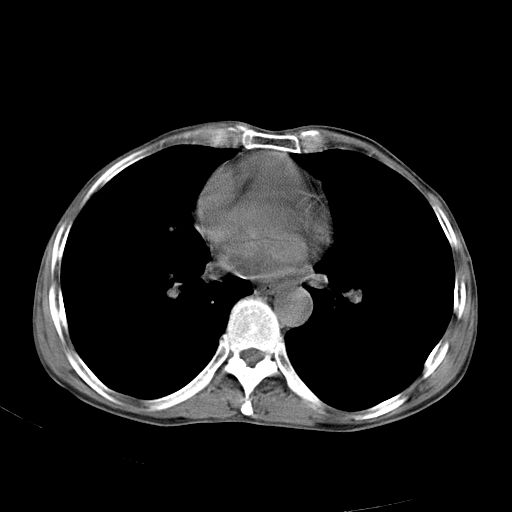

以下是引用苯小孩在2007-5-24 12:47:00的发言:[br]右侧肺门处不均匀密度软组织块影,远端肺组织见斑片模糊影,纵隔内淋巴结明显肿大,边界不清.<纵隔窗第12层面支气管内似见软组织结节>[br]考虑:1、右侧中央性肺癌并阻塞性肺炎并纵隔淋巴结转移可能性大.建议强化或纤支镜进一步检查.[br]2、隆突下淋巴结肿大/食道病变?请做鉴别检查.

以下是引用zhangzhongshou在2007-5-24 12:55:00的发言:[br]1、右肺中叶中心型肺癌并右肺门、隆突下、纵隔淋巴结转移。右肺中叶阻塞性肺炎。

以下是引用jw-830在2007-5-24 15:24:00的发言:[br][br] [br] 考虑右肺中央型肺癌并阻塞性炎症,右肺门及纵隔淋巴结转移。 [br] [br][br]